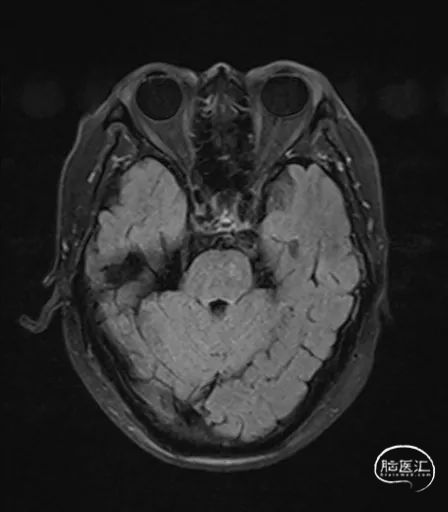

MRI提示小脑缺血性改变。

术后CT:未见明显脑出血,双侧小脑低密度影。

术后9天MRI: